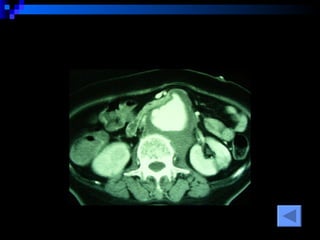

CT SCAN AAA juxtrareal -> bifurcation  Size 10*8*4 cm Inflamatory tissue  around AAA Intact renal artery Aortic dissection at juxtra renal -> bifurcation Bowel wall thickening at 3 rd -4 th  part of duodenum

CT SCAN AAAjuxtrareal -> bifurcation Size 10*8*4 cm Inflamatory tissue around AAA Intact renal artery Aortic dissection at juxtra renal -> bifurcation Bowel wall thickening at 3 rd -4 th part of duodenum